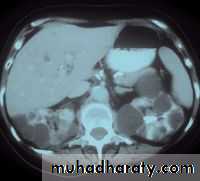

CT also shows enlarged kidneys with multiple cysts appears as low attinuated areas

Poly cystic kidney